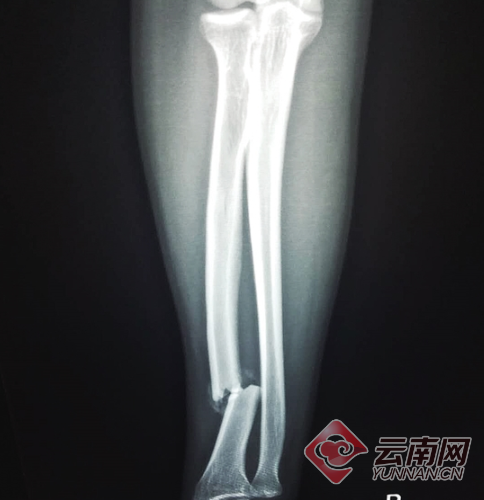

这伤,惨不忍睹

“带我去医院吧。”面对小伙的要求,驾驶员开车将其送到西山区人民医院。照了胸片和CT,CT结果显示伤者右手桡骨骨折。